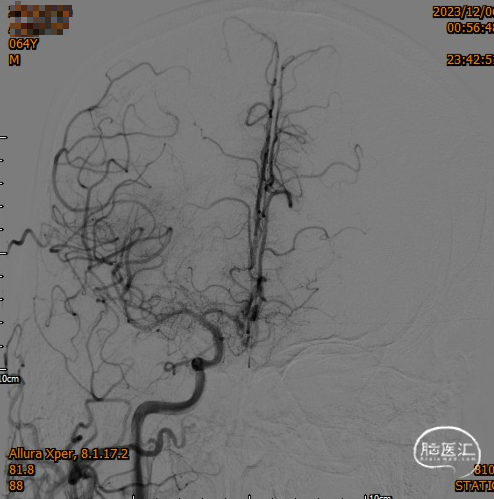

造影,颈内动脉未见血栓,颅内动脉较前未见明显减少,无明显血栓逃逸。

复查造影支架成形良好,颅内较前无明显改变,未发现血管减少影像,供血较前明显改善。